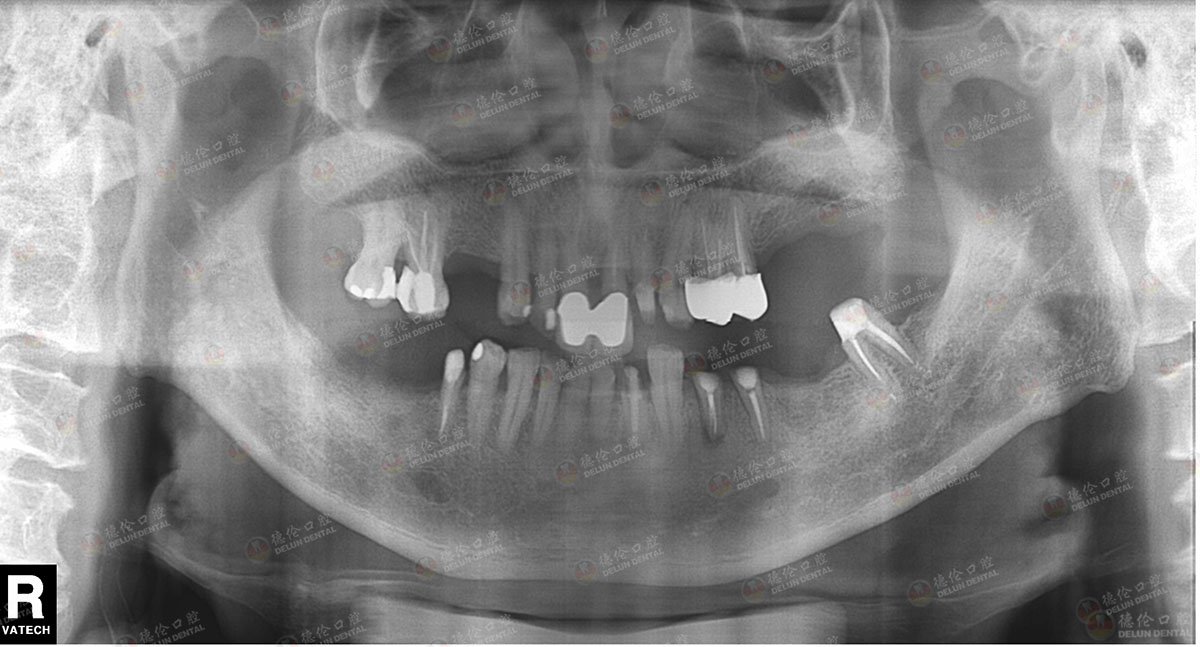

牙齿症状:门牙缺失两颗、后牙多颗缺失

治疗方法:数字化3D导板种植

利用3D导板固定,种植两颗门牙